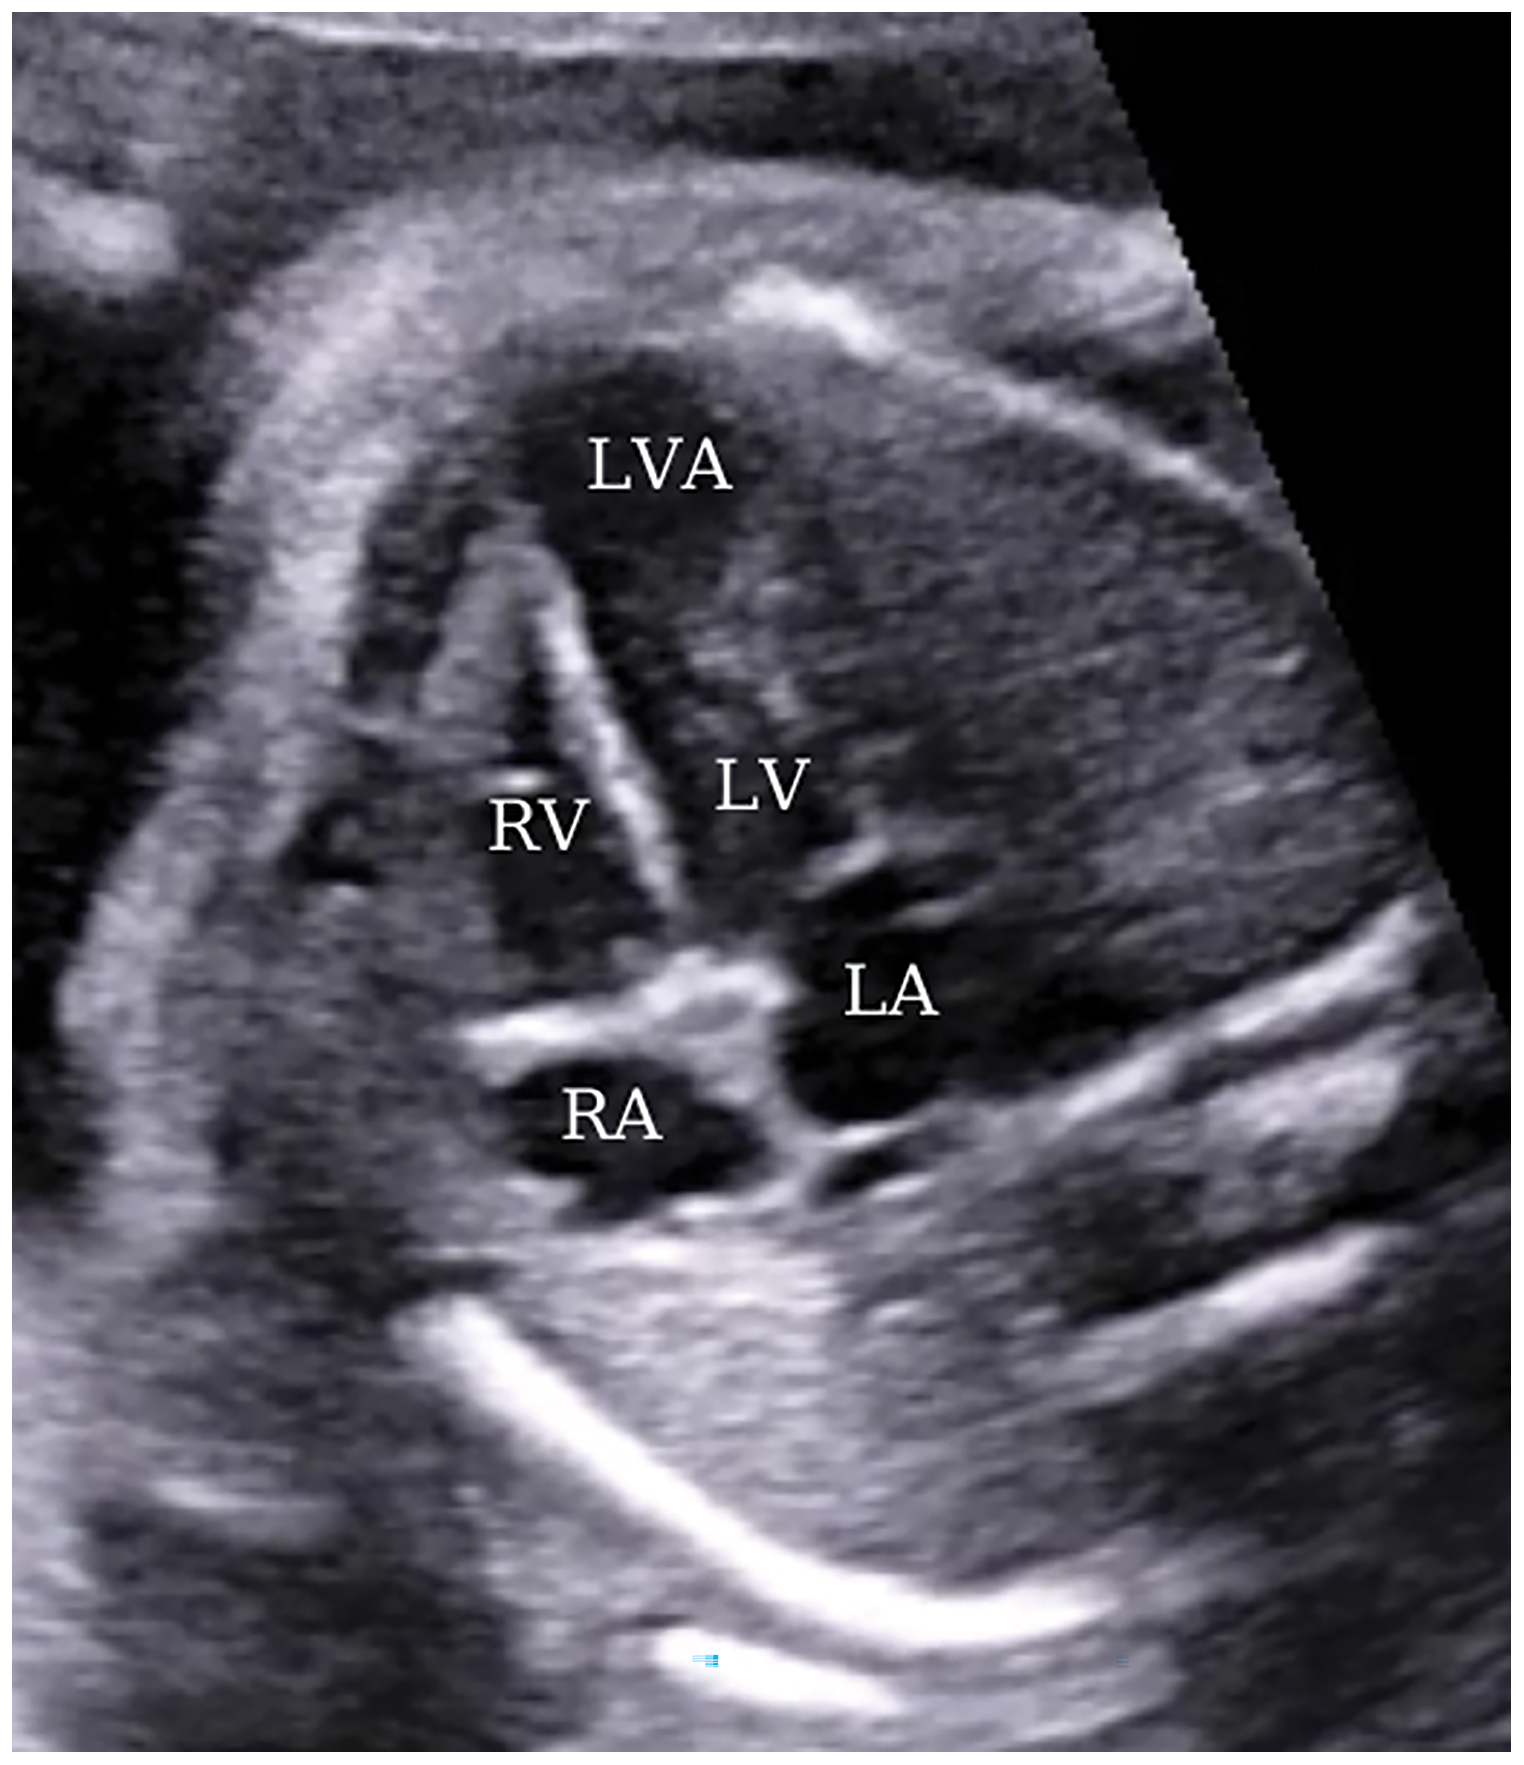

A 35-year-old patient, gravida 2, parity 1, pregnant in the 24th gestational week was referred for abnormal cardiac morphology. The patient, who had had a previous cesarean section, had no history of congenital heart disease or any other genetic disease in her medical and family history. Fetal ECHO revealed a large aneurysmatic image opening from the apical wall of the left ventricle (LV) into the left ventricular cavity (Fig. 1).

Figure 1: A view from a four-chamber section displaying an apically located left ventricular aneurysm at 24 weeks of gestation. LA, left atrium; LV, left ventricle; RA, right atrium; RV, right ventricle; LVA, left ventricular aneurysm